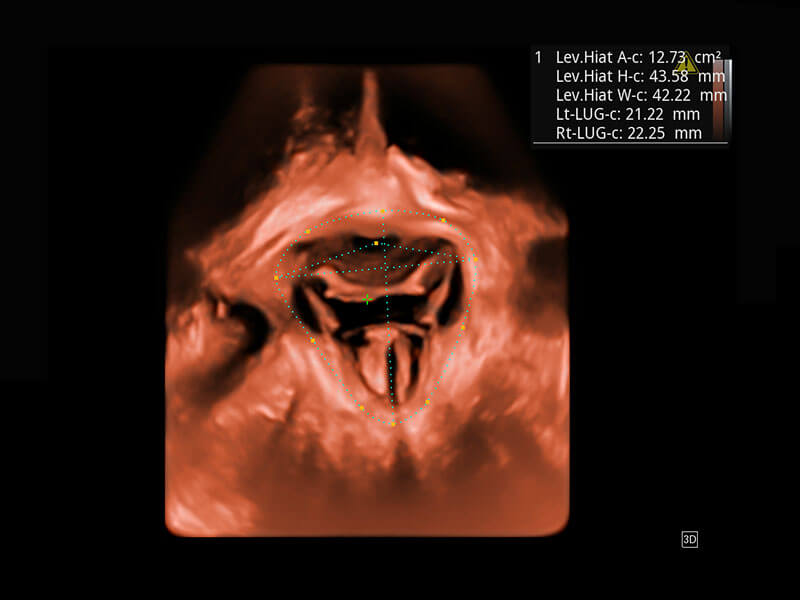

P60為盆底超聲檢查提供應(yīng)用方案,多種腔內(nèi)及腹部容積探頭提供從二維、三維到四維的優(yōu)異圖像品質(zhì),實(shí)時(shí)快速三維容積數(shù)據(jù)獲取,專業(yè)的測(cè)量工具包等人性化設(shè)計(jì),為超聲醫(yī)生診斷提供有力保障。

Lev.Hiat A-r: 16.33 cm2

Lev.Hiat H-r: 53.70 mm

Lev.Hiat W-r: 43.96 mm

Lt-LUG-r: 24.16 mm

Rt-LUG-r: 19.94 mm

能夠簡(jiǎn)化盆底檢查的操作流程,可在二維模式及三維成像模式下實(shí)現(xiàn)一鍵自動(dòng)提取出標(biāo)準(zhǔn)切面、自動(dòng)識(shí)別當(dāng)前切面、自動(dòng)測(cè)量,提升盆底檢查的高效性,同時(shí)也能讓青年醫(yī)生快捷的獲得準(zhǔn)確的檢查結(jié)果。